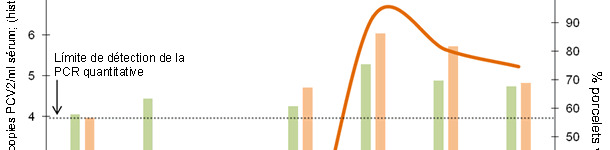

Cet article explique les facteurs à prendre en compte pour déterminer le moment optimum de la vaccination contre le PCV2 et montre les résultats d'une étude qui mesure l'efficacité de différents programmes vaccinaux dans un élevage avec une infection subclinique.

Dans le scénario étudié, les pertes occasionnées par une croissance plus faible atteignent 13,1 et 7,5 €/tête pour les porcs avec, respectivement, une charge de PCV2 haute et moyenne.

La façon la plus efficace d'éviter des pertes productives associées au PCV2 est d'éviter que la virémie se produise en indusant une immunité passive ou active qui minimise la circulation du virus dans l'élevage.